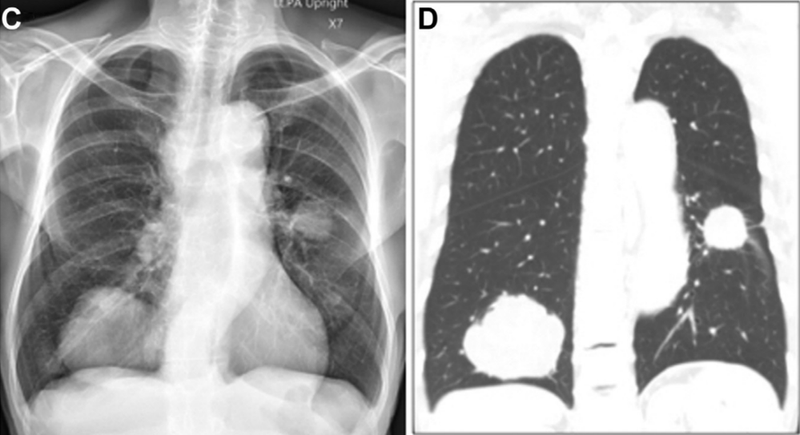

胸片和胸部CT扫描(下图C和D)可见右下叶有一大团块,左下叶有一个小团块,右下叶团块大小是5.0cm*4.3cm*6.5cm,有分叶,增强后不均匀强化。